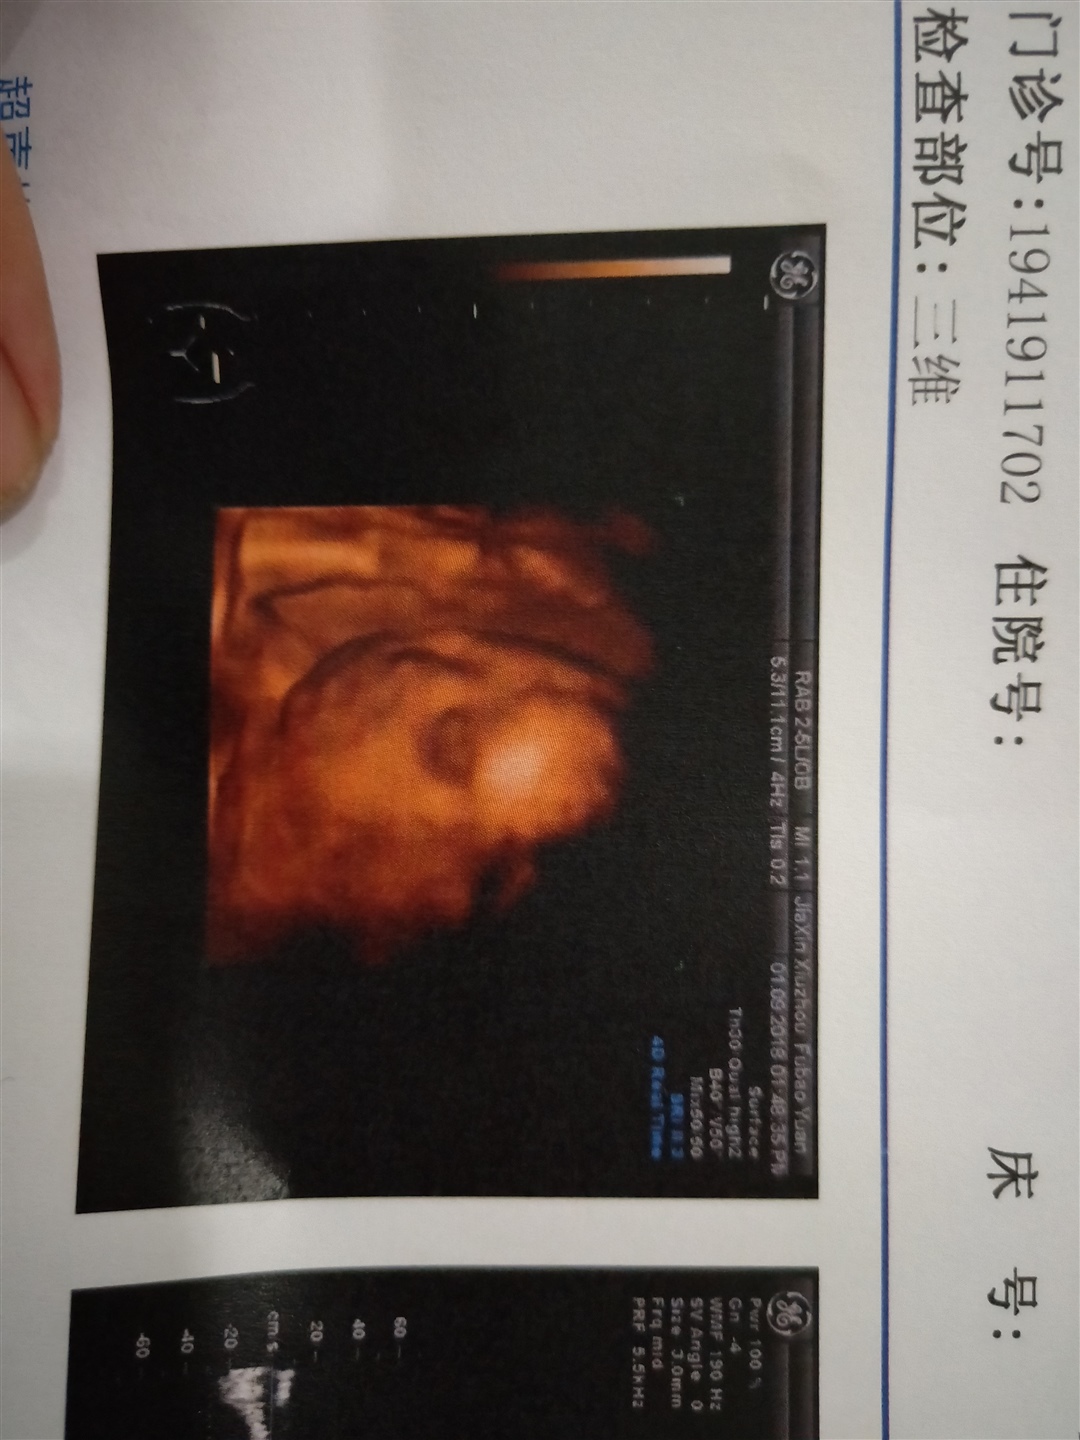

孕31周+4天

男宝

孕26周+3天